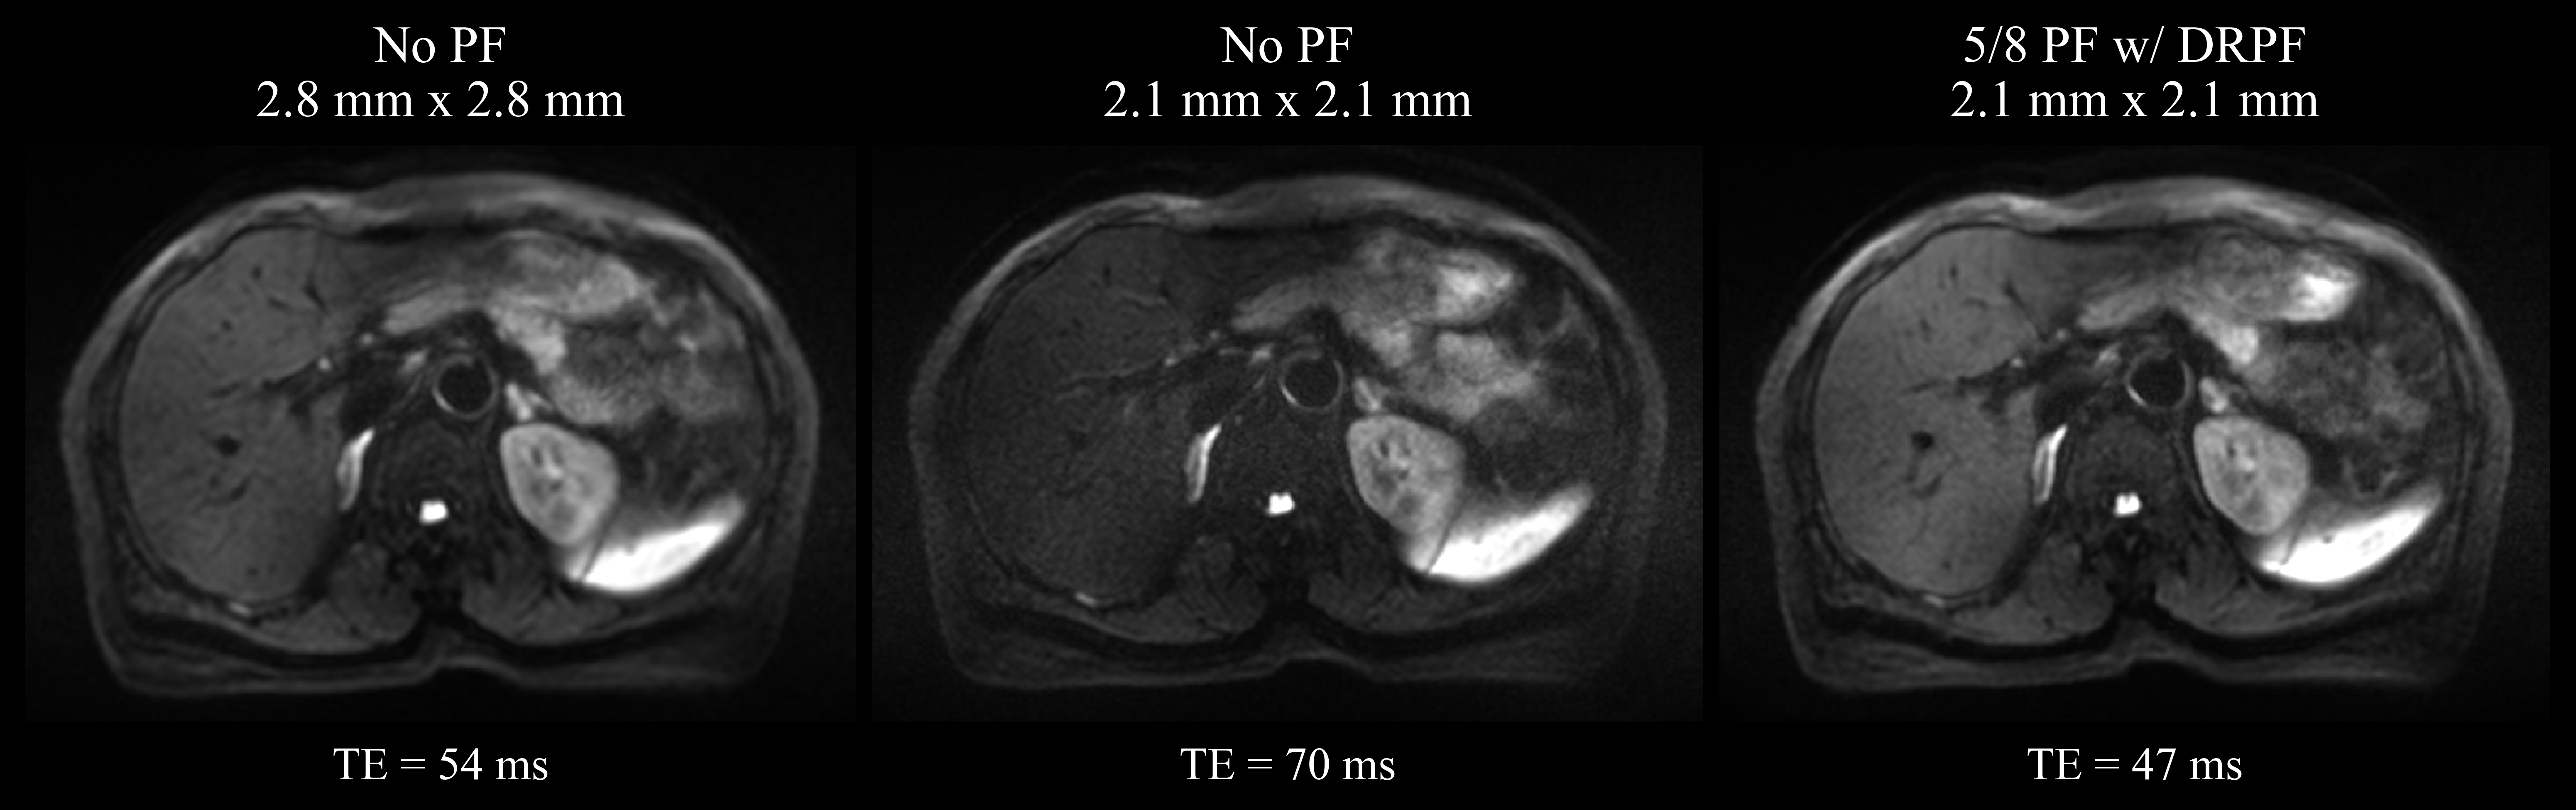

Figure 6 illustrates the effect of combining the proposed PF reconstruction with an acquisition of higher spatial resolution. Using a prospective PF-sampling of 5/8, TE can be reduced by almost one third. In fact, the resulting TE is even shorter than for a non-PF acquisition with the lower resolution. Consequently, by applying the proposed method to the sub-sampled data set, the reconstructed high-resolution image is comparable in SNR to the lower resolution image while not exhibiting visible sacrifices in terms of image sharpness compared to the high-resolution image acquired without PF.

Refer to caption

Figure 6: Qualitative comparison of three acquisitions at 3 T displayed with identical windowing: (left) standard resolution without PF-sampling, (middle) higher resolution without PF-sampling and (right) higher resolution with a PF-sampling of 5/8 reconstructed by the proposed method. Below each image the corresponding echo times are shown which were chosen as minimal as possible while leaving the TR constant across all three acquisitions.

In order to validate the reconstruction quality of the proposed method on prospectively PF-sampled data, three additional data sets were acquired using a PFF of 5/8. Further, the effect of PF-induced TE reduction was demonstrated by comparing the data of a selected volunteer from the test set with two additionally acquired scans of the same volunteer with higher spatial resolution: one without PF-sampling and one with prospective PF-sampling of 5/8. Compared to the data set with standard resolution, the matrix size was increased from 134Γ—108134108134\times 108 to 180Γ—146180146180\times 146 while keeping the FOV constant, corresponding to an isotropic resolution increase from 2.8 mm to 2.1 mm for both acquisitions. Keeping TR fixed, TE was chosen as minimal as possible in all scans. A detailed comparison of relevant acquisition parameters is provided in Supporting Information Table S1.

LR w/o PF HR w/o PF HR w/ 5/8 PF

FOV (mm2) 380Γ—308380308380\times 308 380Γ—308380308380\times 308 380Γ—308380308380\times 308

Matrix size 134Γ—108134108134\times 108 180Γ—146180146180\times 146 180Γ—146180146180\times 146

Resolution (mm2) 2.8Γ—2.82.82.82.8\times 2.8 2.1Γ—2.12.12.12.1\times 2.1 2.1Γ—2.12.12.12.1\times 2.1

TR (ms) 6,300 6,300 6,300

TE (ms) 54 70 47

Table S1: Comparison of relevant parameters of the DWI acquisitions described in 3.3.2 collecting data of low (LR) and high resolution (HR) with and without prospective PF-sampling.